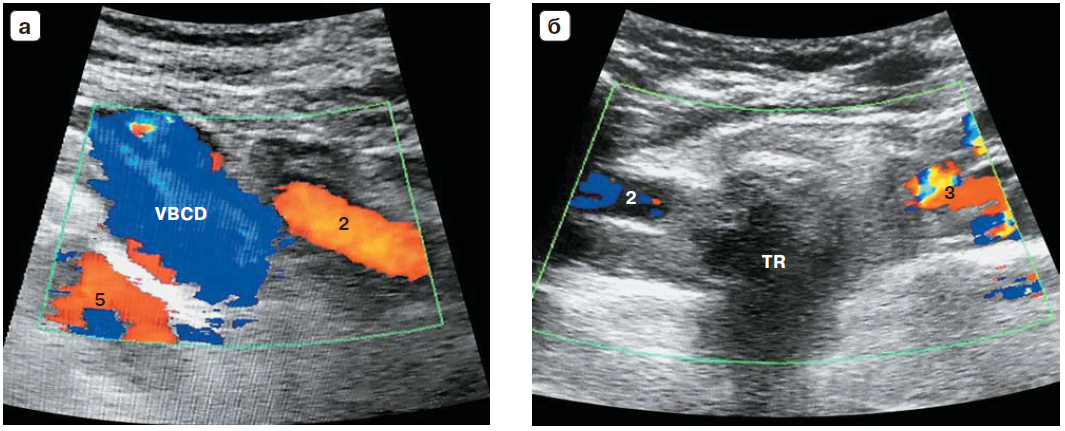

Рис. 3. Компьютерная томография: а – трехмерная реконструкция (вид спереди); б – трехмерная реконструкция (вид сзади); в – сагиттальный срез на уровне срединной линии тела; г – схема: 1 – дуга аорты, 2 – правая общая сонная артерия, 3 – левая общая сонная артерия, 4 – левая подключичная артерия, 5 – a. lusoria, TR – трахея, E – пищевод.

Рис. 4. УЗИ с цветным картированием. Отсутствие Y-признака: а – общая сонная и правая подключичная артерии не объединяются в брахиоцефалический ствол; б – общие сонные артерии находятся в одном направлении (косвенный признак); 2 – правая общая сонная артерия, 3 – левая общая сонная артерия, 5 – a. lusoria, TR – трахея, VBCD – правая брахиоцефалическая вена.